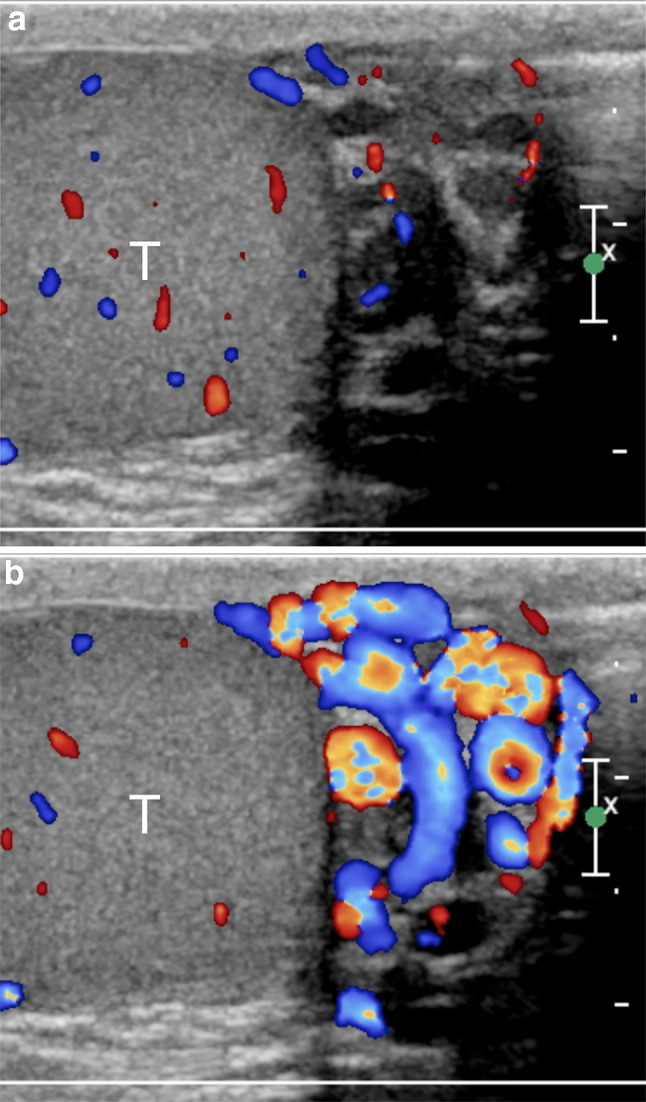

One of the problems encountered when comparing different US studies for varicoceles concerns the variability of reporting. A standard report should be useful, in which all the relevant data are collected. The variable clinical practice in reporting patients with varicoceles reflects the differences in examination techniques. The ESUR-SPIWG recommends describing the examination technique and reporting all the US parameters used to evaluate the patient. It also suggests grading varicoceles according to the Sarteschi’s classification (Figs. 3, 4, 5, 6, Table 2, recommendations 12–13).

Fig.3.

Sarteschi’s grade I varicocele. Colour Doppler images obtained at rest (a) and during Valsalva (b) showing dilated veins of the spermatic cord with reflux during Valsalva at the inguinal canal

Fig.4.

Sarteschi’s grade II varicocele. Colour Doppler images obtained at rest (a) and during Valsalva (b) showing dilated veins in the supratesticular region with reflux during Valsalva (T = testis)